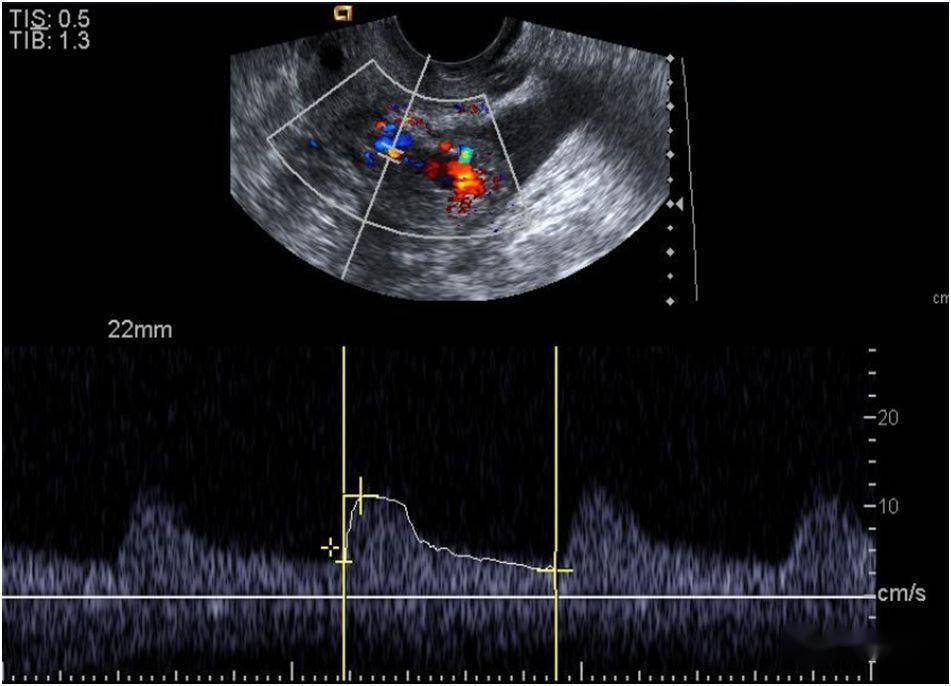

子宫穿孔超声表现图

子宫穿孔超声表现图,子宫穿孔超声图片

超声典型病例子宫穿孔

子宫穿孔的超声诊断

高手进阶:子宫穿孔的超声诊断

子宫穿孔彩超下表现

子宫穿孔彩超图